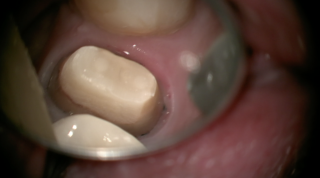

そのため、その歯に被せ物をする場合には、大きく欠損した部分を補填して土台を作る必要があります。

治療した歯の根の上に、土台を作って初めて被せ物ができます。

実は、この『土台』は、最終的には被せ物の下に隠れてしまうものですが、歯が長持ちするかを左右するとても大事なものなのです。

ファイバーコア(樹脂の土台)は、型採りを必要としませんので、土台の歯にダイレクトに樹脂を盛り上げることができるので、歯を削る量を最小限にすることができます。

更に、ファイバーコアは、硬さがメタルコアよりも歯の硬さに近いので、メタルコアより歯が割れにくいのも大きなメリットです。

そして、ファイバーコアは光を通す特徴があります。白い被せ物(クラウン)では光を通さないメタルコアより、より自然な色を再現することができます。